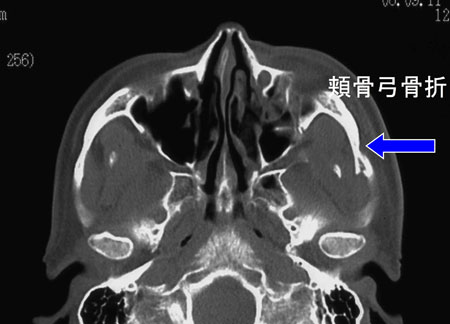

3.頬骨骨折

ほほの骨の骨折です。

頬骨骨折